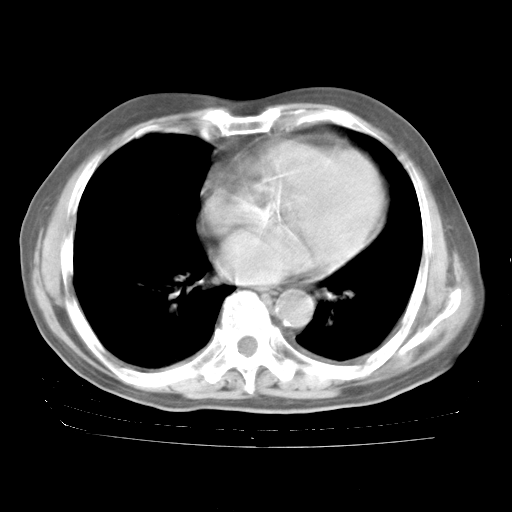

4月28日肺部CT